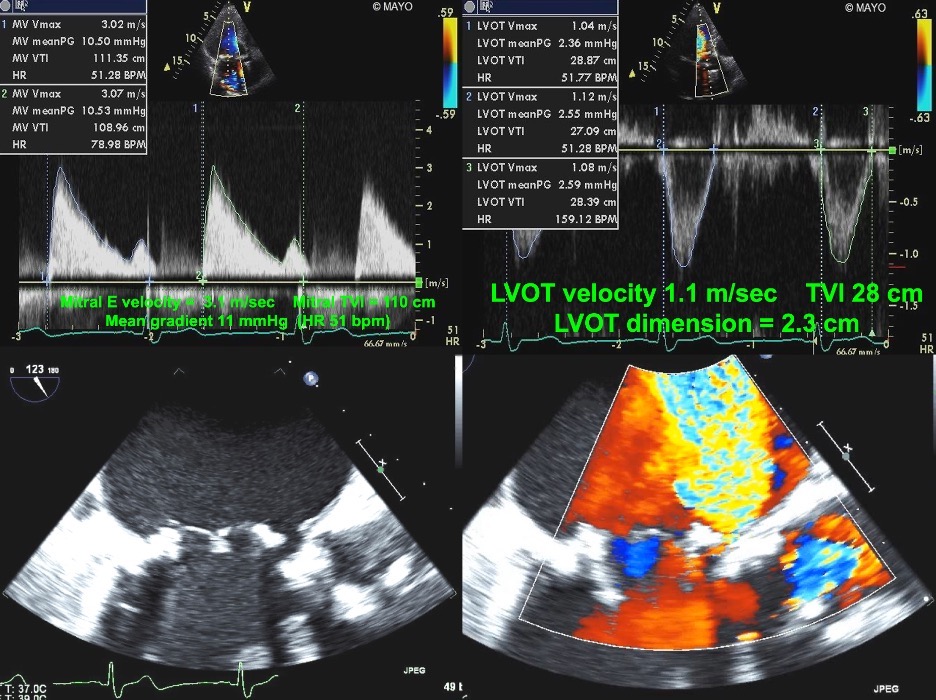

Progressive stenosis will lead to a prolonged acceleration time (AT), which is the time to the peak of the jet velocity as a result of delayed peaking of the velocity during systole. Therefore, the Doppler profile contour of an aortic prosthesis with stenosis with thrombi or pannus formation will be blunted and rounded as opposed to the triangular shape characteristic of a normally functioning prothesis (Figs. 4,5). This can be quantified by the ratio of the AT to the total ejection time (ET) over which blood flow occurs during systole, as a normal AT/ET ratio is less than 0.32. The AT as well as the AT/ET can also help distinguish true prosthetic obstruction from other conditions that confer a “functional” obstruction such due to high flow states (which can result from anemia, thyrotoxicosis, AV fistulas, or significant aortic regurgitation), pressure recovery, or patient prosthesis mismatch that can also lead to an elevated mean aortic prosthetic gradient. A functional obstruction will present with a peak velocity greater than 3 m/s, but the AT will be less than 80 ms, and the AT/ET, though it may be mildly elevated will not typically be greater than 0.37 [50, 51].

Fig. 4.Continuous Wave Doppler of a normally functioning aortic prosthesis with functionally obstructive hemodynamics. Note the triangular contour of the Doppler jet with a rapid acceleration time (AT) of 70 msec.